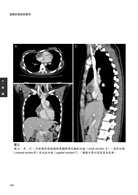

病例6 內固定骨釘異位(Malposition of internal fixation pin) 26